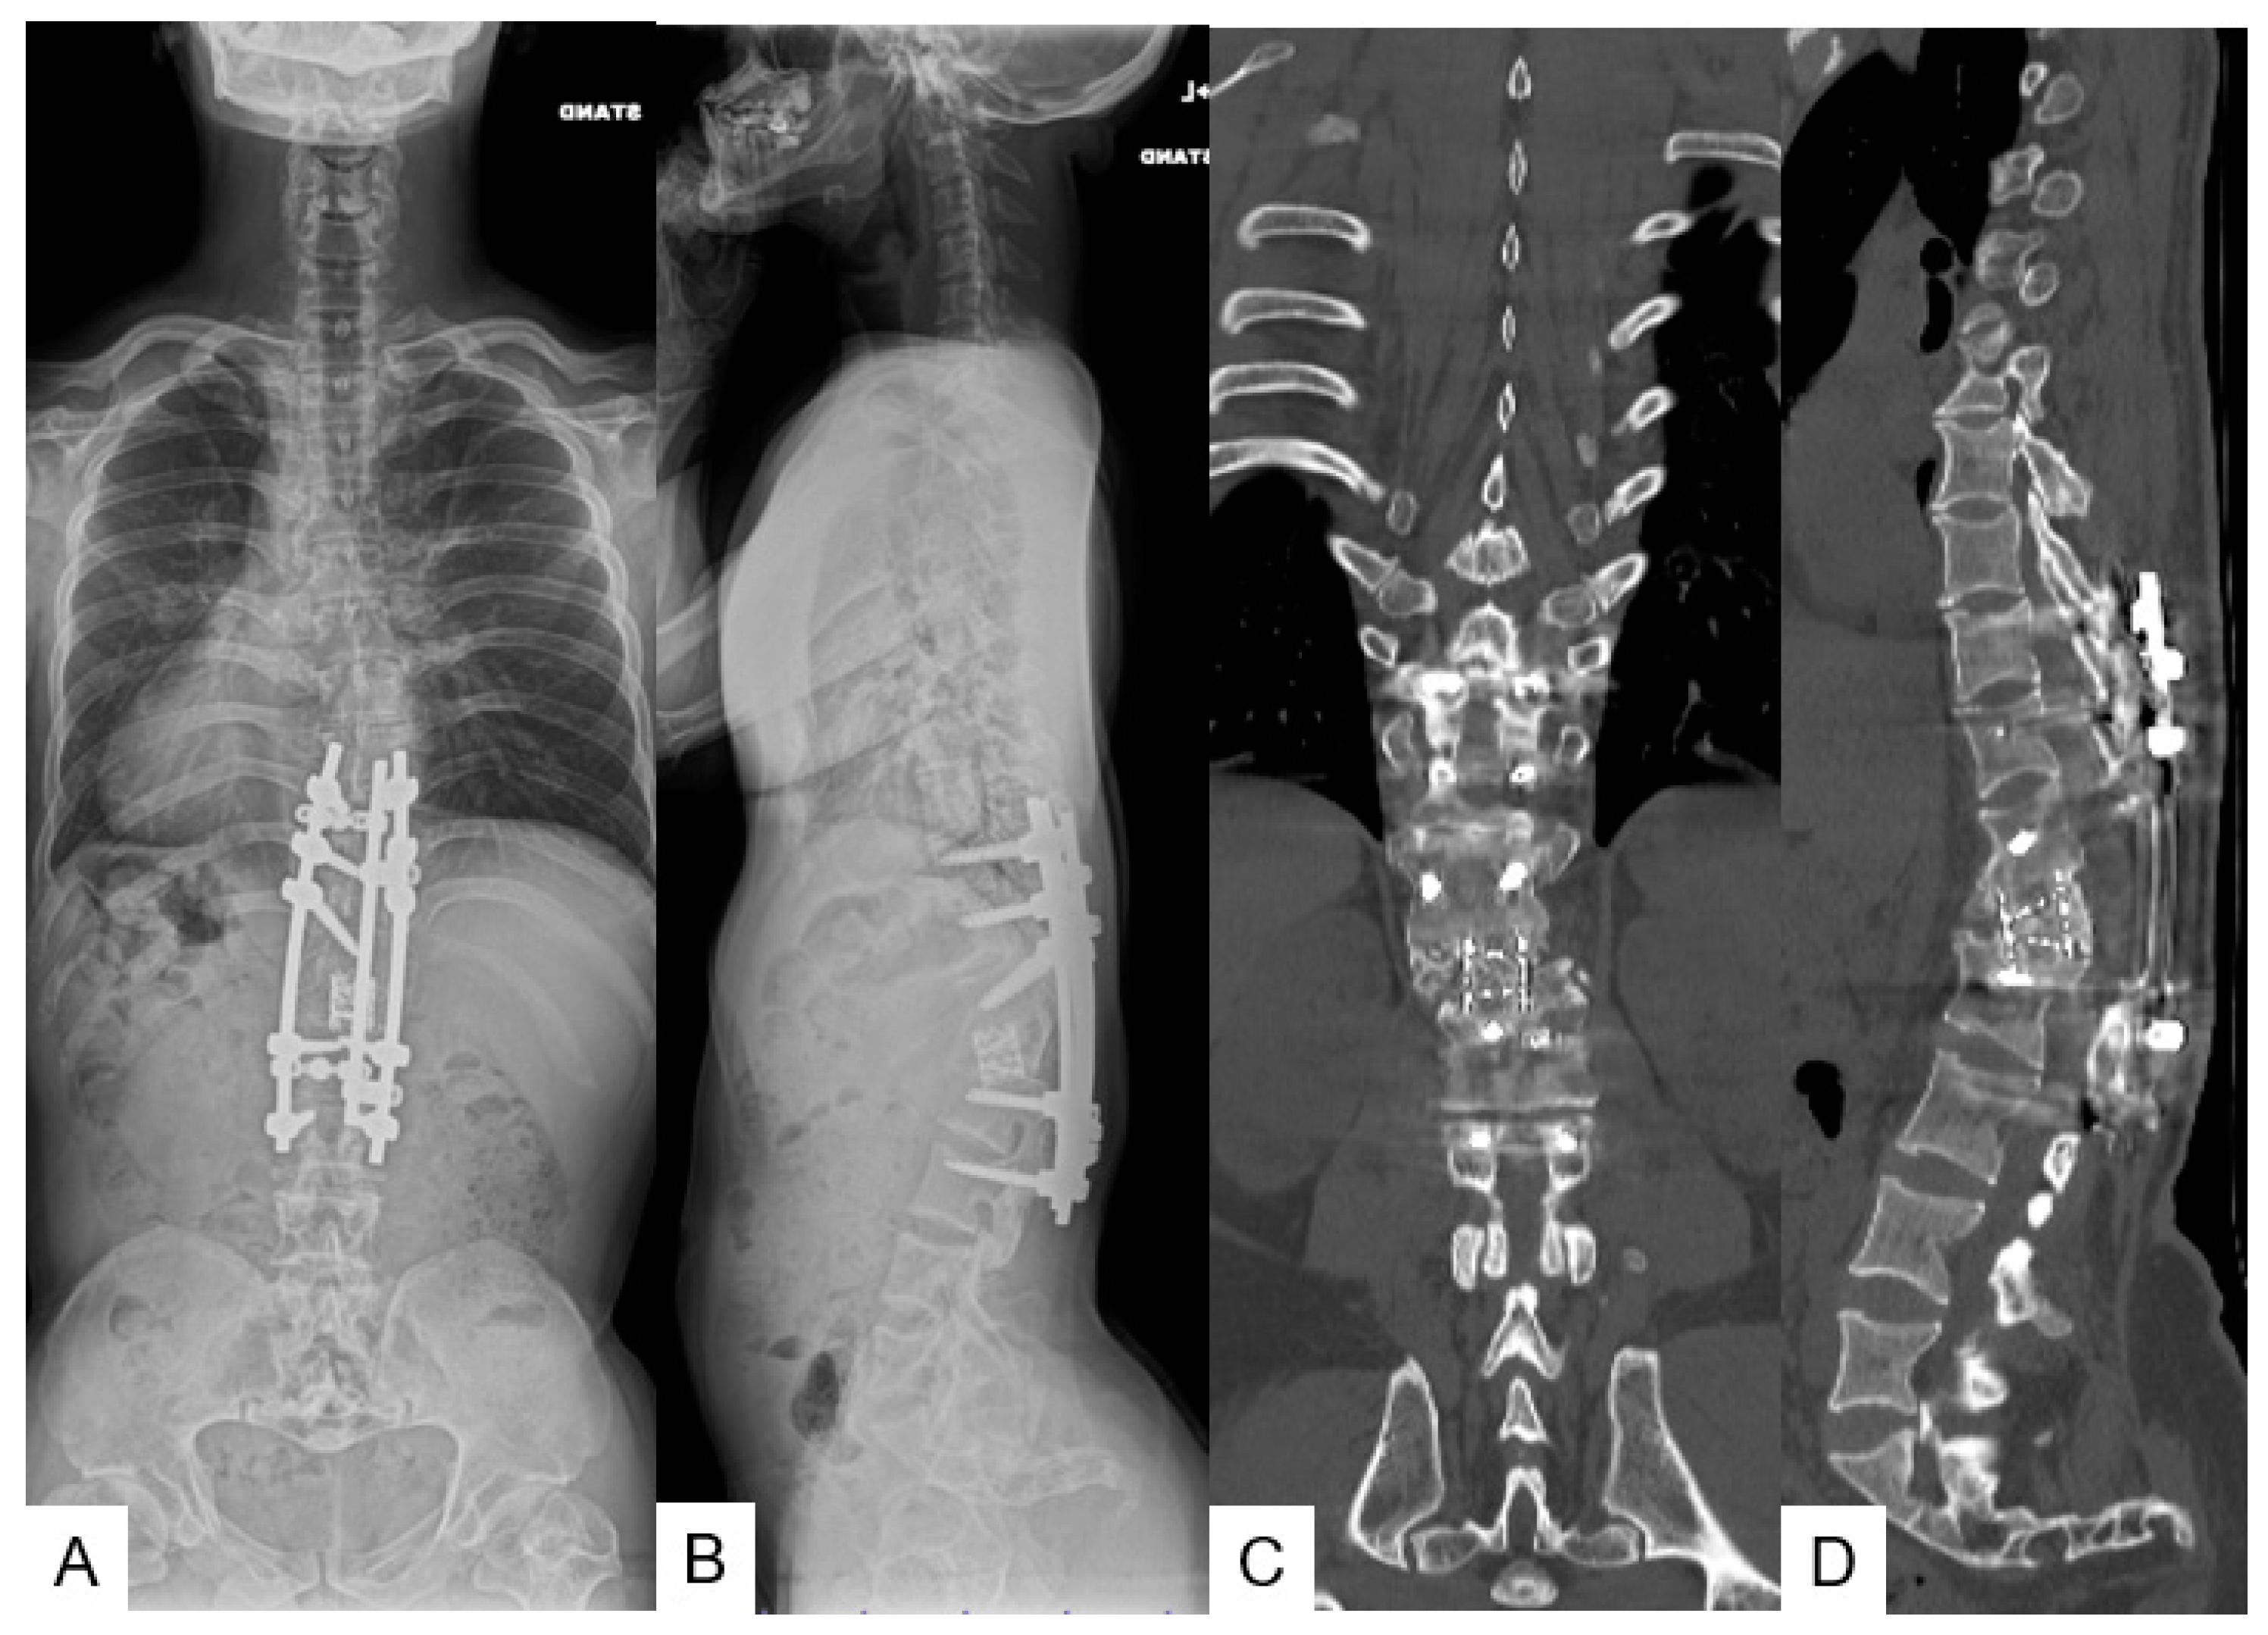

3.3.5. Postoperative Imaging

3.3.6. Follow-Up Results